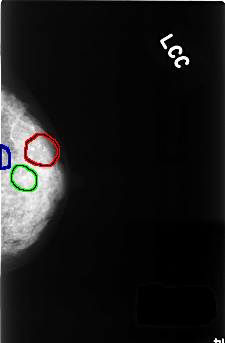

C_0375_1.LEFT_CC

LEFT_CC LINES 4456 PIXELS_PER_LINE 2920 BITS_PER_PIXEL 12 RESOLUTION 50 OVERLAY

FILE: C_0375_1.LEFT_CC.OVERLAY

TOTAL_ABNORMALITIES 3

ABNORMALITY 1

LESION_TYPE CALCIFICATION TYPE PLEOMORPHIC DISTRIBUTION CLUSTERED

ASSESSMENT 4

SUBTLETY 5

PATHOLOGY BENIGN

TOTAL_OUTLINES 1

BOUNDARY

ABNORMALITY 2

ABNORMALITY 3